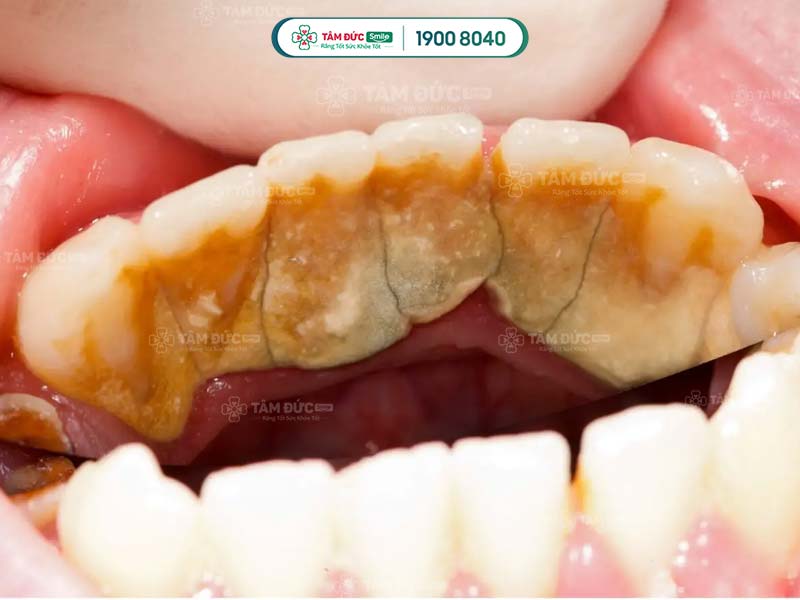

- Phát hiện có nhiều cao răng và mảng bám ở thân răng hoặc dưới nướu.

Cao răng không phải là nguyên nhân trực tiếp gây ra các bệnh lý về răng miệng, nhưng lại là nơi trú ngụ của nhiều loại hại khuẩn. Vì vậy, cao răng tạo điều kiện để vi khuẩn gây bệnh.

Cao răng tích tụ lâu ngày sẽ gây ra các bệnh lý như: Sâu răng, viêm nướu, tụt nướu, mòn men răng, viêm nha chu,... Do đó, cạo cao răng thường xuyên giúp Quý khách ngăn chặn vi khuẩn phát triển, giảm nguy cơ mắc phải các bệnh lý răng miệng.

Cao răng có màu sẫm, tích tụ trên thân răng làm ảnh hưởng đến thẩm mỹ nụ cười. Cạo cao răng giúp Quý khách loại bỏ các mảng bám tối màu, trả lại hàm răng trắng sáng và đẹp mắt hơn.